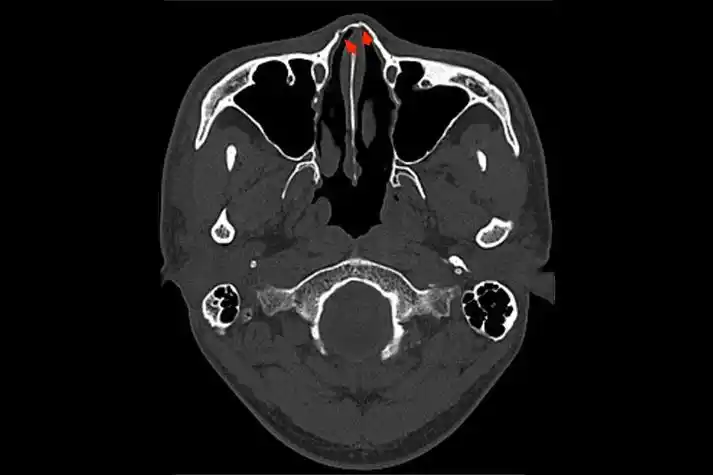

鼻骨解剖及ct诊断

鼻骨正常ct解剖,变异与骨折